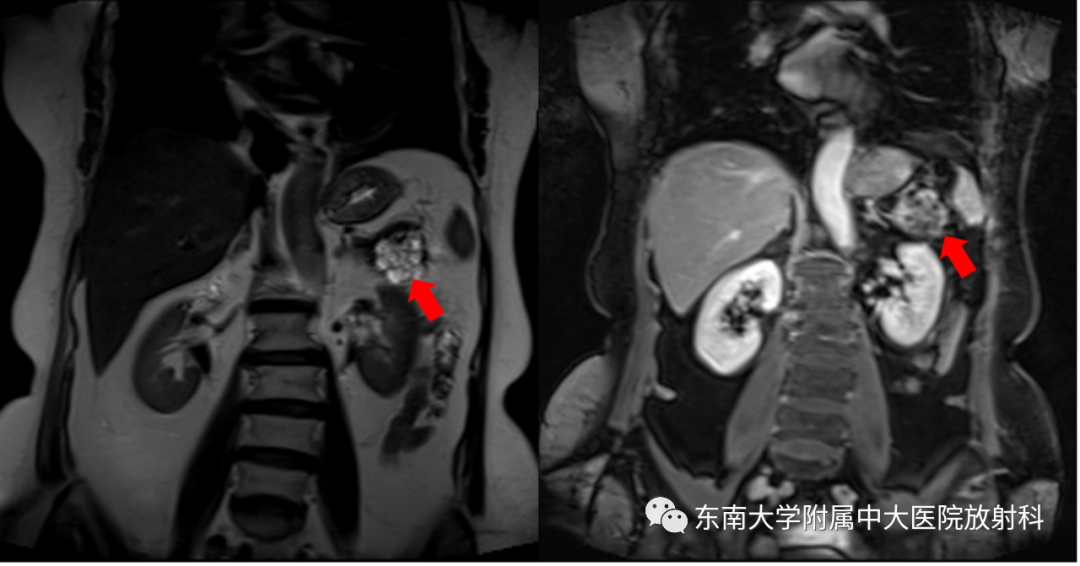

女,78岁

主诉:发现胰腺占位性病变1月余

既往史:高血压病史25年,冠心病病史25年

CT平扫+增强

MRI平扫+增强